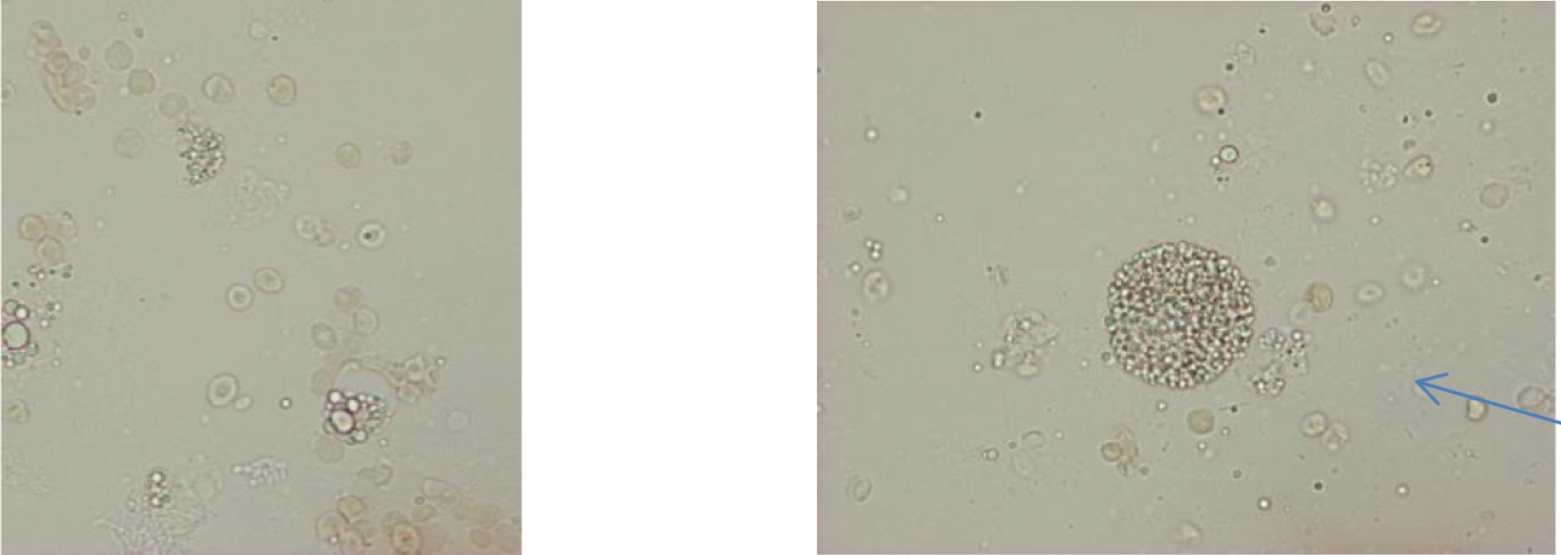

Fatty cast

Renal tubular cast

WBC cast

RBC cast

Waxy cast

Granular cast

Hyaline cast